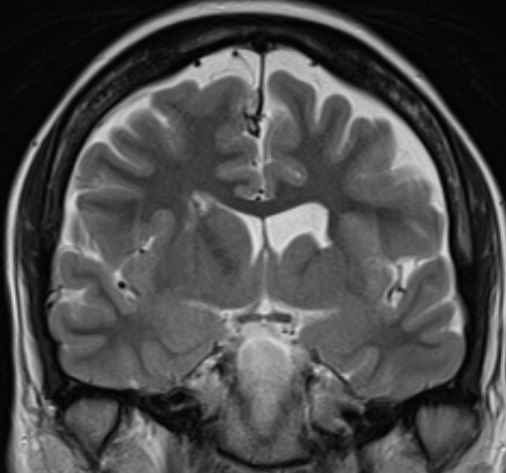

The structural correlates of the above EEG findings appear below. There is enlargement of the left-ventricular system, atrophy of the head, body and tail of the caudate nucleus and the left hemisphere appears modestly smaller in size than the right, most evident on axial sequences. The MRI was done while the patient was quite restless. As you can see from these pictures, the left occipital cortex and the left thalamus do not demonstrate any structural correlate to the asymmetry of alpha rhythms. However, we know from the EEG that the left hemisphere is markedly dysfunctional. Unsurprisingly, on functional MRI scans language is represented in the right hemisphere.